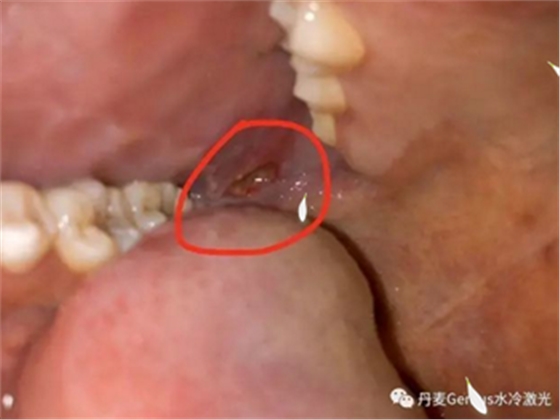

淺表黏膜膿腫切開引流

在常規(guī)消毒后,涂抹本品,再行切割。在更換藥物時,也可以涂抹